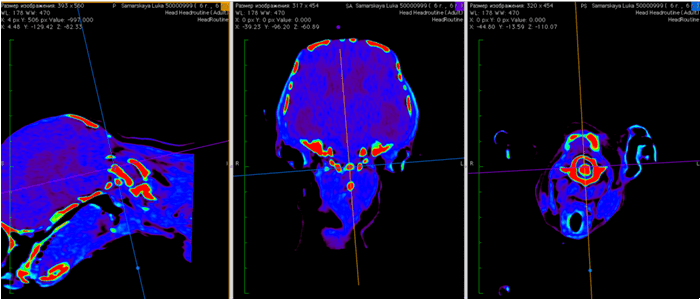

На мрт исследовании нашего пациента – здесь представлена сагитальная Т2 взвешенная последовательность, определяется смещение аксиального позвонка в дорсальном направлении по отношению к атланту, дислокация дорсальной дужки атланта к задней черепной ямке с тяжелой компрессией как мозжечка, так и спинного мозга.

Мрт пациента с краниоцервикальной мальформацией (Впадина Дьюи, сирингомиелия в шейном отделе)